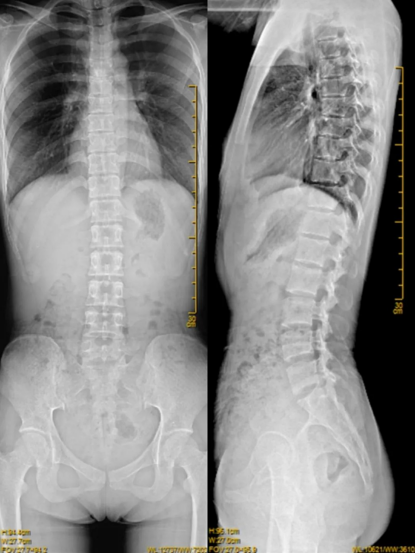

臨床在診治脊柱及下肢畸形時(shí),一些病情嚴(yán)重的患者往往需要手術(shù)矯正治療,這就需要對(duì)其進(jìn)行手術(shù)前后拍攝全脊柱或全下肢的X光片作為依據(jù),以便分析病情、制定手術(shù)方案和評(píng)估術(shù)后療效。目前廣大青少年及學(xué)生由于學(xué)業(yè)負(fù)擔(dān)重,時(shí)常接觸電子產(chǎn)品,更加容易出現(xiàn)脊柱側(cè)彎畸形等病變,脊柱全長(zhǎng)的攝片能及早地發(fā)現(xiàn)脊柱側(cè)彎及側(cè)彎的程度,及早地進(jìn)行臨床干預(yù)及治療。

常規(guī)DR攝片機(jī)拍攝面積有限,最大規(guī)格僅有43cm,但成人男性全脊柱長(zhǎng)度平均為70-75cm,女性為66-70cm,而全下肢更長(zhǎng)。常規(guī)攝片技術(shù)不能一次性拍攝出完整的全脊柱或全下肢的X光影像。例如在沒(méi)有拼接技術(shù)以前,全脊柱的拍攝需要分別拍攝頸椎、胸椎、腰椎的X光片,雖然能夠觀察到局部的側(cè)彎情況,但不能觀察到三者之間的連續(xù)性,這就增加了這類(lèi)疾病的診治難度。

而這醫(yī)用數(shù)字X射線攝影系統(tǒng),具有影像自動(dòng)拼接功能,一次最多可實(shí)現(xiàn)4張影像的拼接任務(wù),拍攝長(zhǎng)度可達(dá)145cm,使全脊柱及全下肢能夠得到完整清晰的成像。拼接圖像后處理技術(shù),可以為醫(yī)生提供高精準(zhǔn)度的臨床數(shù)據(jù),對(duì)于脊柱側(cè)彎的診斷治療的制定有著重要的參考價(jià)值。雙下肢負(fù)重位全長(zhǎng)拼接攝影能夠觀察雙下肢、髖關(guān)節(jié)及膝關(guān)節(jié)的病變程度范圍及整體形態(tài),對(duì)于髖、膝關(guān)節(jié)矯形手術(shù)及人工關(guān)節(jié)置換術(shù)等都有著非常重要的指導(dǎo)意義,為臨床治療提供重要參考依據(jù)。全脊柱及下肢全長(zhǎng)拼接攝影技術(shù)的成功開(kāi)展,能使患者得到科學(xué)的診斷及治療,為百姓提供更優(yōu)質(zhì)的服務(wù)。